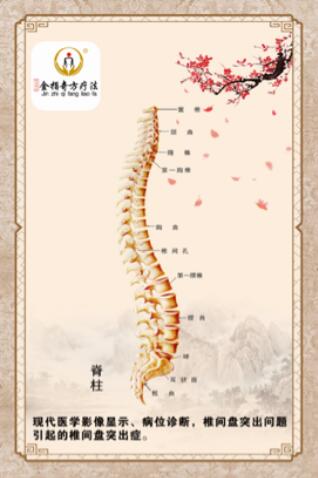

我们通过现代医学X光片、Ct、磁共振影像显示,病位诊断看到的只是椎骨、生理曲度、椎骨间盘结构问题。

我在上面讲过了,椎间盘突出症是"筋出槽、不能固骨、骨错缝、形态失衡"造成的症疾,不是大家的骨头突出,是支撑我们上肢"脊梁骨"两节椎骨之间形同圆盘状的夹层组织,西医医学名一一椎间盘突出了,椎间盘如同承重墙两块砖间的水泥沙灰夹层,其外围是坚硬性的纤维环,包裹着含水量极高、富有弹性的"果冻”状组织,西医医学名一一䯝核而组成。椎间盘环裹的纤维环在受退行、外力等因素的影响作用下出现凸隆、破裂,髓核顺势从损伤处凸隆、结构呈膨出状态;从破裂处挤溢出来,生理结构呈出壳突出状态。就如同自行车外胎出现破损、内胎露出来样的形态。